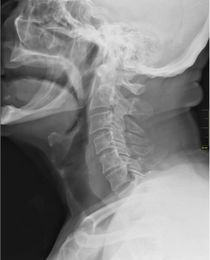

X-ray showing the throat, seen as a dark band to the front of the spine. | |

الحلق (بالإنجليزية: Throat)، في علم التشريح، هو الجزء الداخلي من الرقبة، أمام الفقرات العنقية. ويحتوي على البلعوم (بالإنجليزية: pharynx) والحنجرة (بالإنجليزية: larynx).

ومن المميزات الرئيسية للحلق هو وجود لسان المزمار، وهو غضروف مرن يقوم بفصل المريء عن الرغامى، أو ما يعرف بالقصبة الهوائية، كي لا يدخل الطعام والشراب إلى الرئتين.

ويتكون الحلق من أوعية دموية، عضلات متنوعة، المرئ، الرغامى (القصبة الهوائية). وتعتبر عظمتا الرقبة والترقوة العظمتين الوحيدتين الموجودتين في حلق الإنسان.